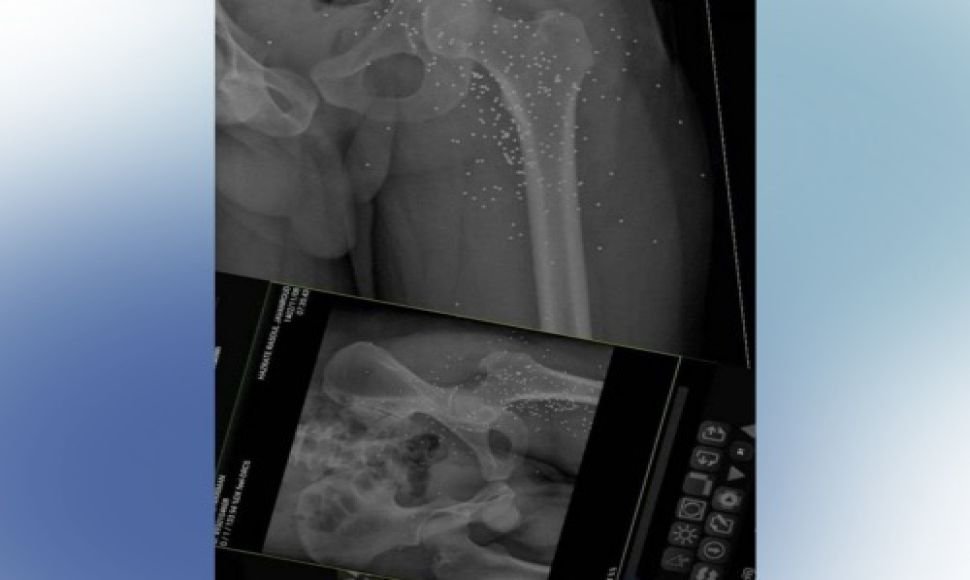

Based on the reports received; On Monday, February 5, 2024, a Kolber with the identity of "Nariman Azizi" from the village of "Ziran" in the province of Javanrood, was seriously injured by the military forces firing with shotguns at the border of Nosud.

As a result of this shooting, Nariman Azizi was seriously injured by more than 600 pellet from the waist down.

According to a source, the doctors had requested a large amount of money to remove the pellets from the body of this Kolber, and the named person had to leave the hospital due to his inability to pay for the treatment.